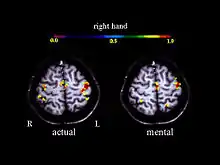

Activation in the motor cortex during motor imagery amounts about 30 % of the level observed during actual performance; Roth et al., 1996.

A large number of functional neuroimaging studies have demonstrated that motor imagery is associated with the specific activation of the neural circuits involved in the early stage of motor control (i.e., motor programming). This circuits includes the supplementary motor area, the primary motor cortex, the inferior parietal cortex, the basal ganglia, and the cerebellum.[21][22] Such physiological data gives strong support about common neural mechanisms of imagery and motor preparation.[23]